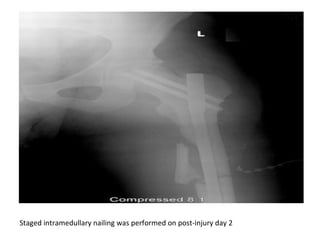

Staged intramedullary nailing was performed on post-injury day 2

Staged intramedullary nailingwas performed on post-injury day 2